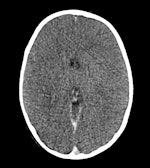

M. Gorincour a fait valoir que, passé un certain délai, tous les cadavres présentaient des traces d'embolie gazeuse, auparavant considérée comme une signature de la cause de décès chez les plongeurs ayant subi des changements de pression rapides. Il a indiqué que cette conclusion pouvait seulement être formulée si l'examen intervenait trois heures après l'accident, et impossible passé six heures.

Il a également découvert que l'emphysème sous-cutané, soit la présence d'air dans les tissus sous-cutanés, pouvait être provoqué par les efforts mis en œuvre pour ressusciter une victime de noyade, sans pouvoir être toujours attribuable à un accident.